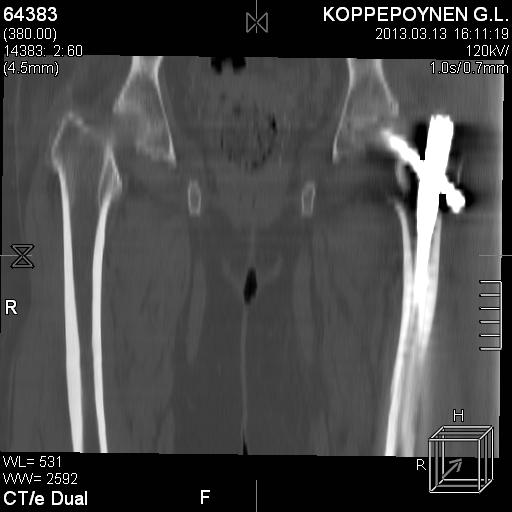

[Ortho] Чрезподвертельный перелом бедра. Остеосинтез стержнем. Перелом металлофиксатора. Дальнейшая тактика?

Делали КТ после операции.